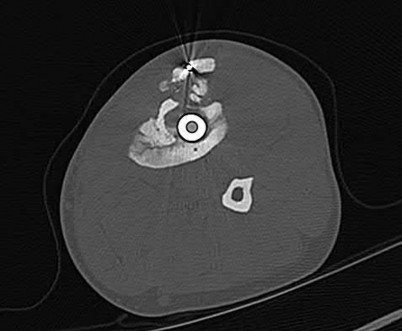

Question 9

A 72-year-old female on prolonged bisphosphonate therapy presents with thigh pain.

Radiographs show a fracture of the femoral shaft. Which of the following radiographic features is most characteristic of an atypical femur fracture associated with bisphosphonate use?

Explanation

Atypical femur fractures (AFFs) associated with prolonged bisphosphonate therapy have specific major criteria defined by the ASBMR. These include a location anywhere from just distal to the lesser trochanter to just proximal to the supracondylar flare, transverse or short oblique orientation, non-comminuted (or minimally comminuted), and originating at the lateral cortex with localized periosteal or endosteal thickening ('beaking').